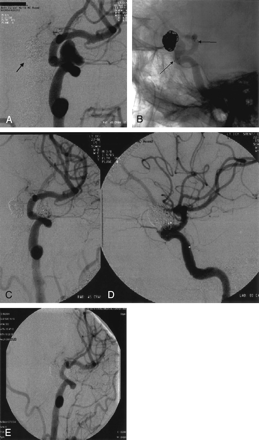

A 58-year-old right-handed woman (case 4) with a history of tobacco smoking and a family member with an intracranial aneurysm was found to have incidental bilateral internal carotid artery (ICA) aneurysms. Eight months after successful coiling of her right ophthalmic aneurysm with pure platinum Guglielmi detachable coils, her left ophthalmic wide-necked aneurysm was treated. Cerebral angiography showed the superiorly directed aneurysm with its origin slightly beyond the left ophthalmic artery. The angiogram showed the aneurysm to measure 11 mm × 7 mm with a 5-mm neck (Fig 2A). Under full heparinization, microcatheterization (Excelsior SL-10, Boston Scientific) beyond the aneurysm was followed by deployment of a Neuroform stent delivery system over an Accelerator 0.014-inch, 300-cm-long exchange microguidewire (Microtherapeutics, Irvine, CA). The stent, measuring 4 mm × 20 mm, was navigated and deployed such that it covered the aneurysm neck and rested from below the anterior choroidal takeoff to the level of the dural ring (Fig 2B). The Excelsior SL-10 microcatheter over a microguidewire was then introduced through the stent into the superior portion of the aneurysmal sac.

A, Left ICA digital subtraction angiography (oblique view) reveals a paraclinoid aneurysm (arrow points to coil mass of right paraclinoid aneurysm coiled 8 months earlier).

B, Digital nonsubtracted angiogram of the left ICA after stent deployment. The stent proximal and distal markers are visualized (arrows) across the aneurysm neck before deployment.

C and D, After HydroCoil embolization, with an excellent angiographic and clinical result. Coils are again seen in the contralateral previously coiled aneurysm.

E, Follow-up angiography 1 year later shows stable coil occlusion of the left paraclinoid aneurysm with no evidence for in-stent stenosis or aneurysm recanalization.

Successive coil placement leading to near complete obliteration of the aneurysm was accomplished by first placing a microplex 2D coil (MicroVention) measuring 10 mm × 24 cm as a frame, followed by packing with six HydroCoils (Fig 2C, –D). Interim repetitive angiography, performed after each coil placement, documented progressive occlusion of the aneurysm secondary to HydroCoil expansion until there was only minimal residual filling of the anterior aneurysm neck and anterior inferior sac with marked stagnation (Fig 2C, D). Control angiography 3 days later demonstrated preserved internal carotid and ophthalmic artery patency and total obliteration of the aneurysm. One year postprocedure, she remains neurologically well and angiography shows a stable configuration of both her coils and stent without evidence for recanalization or in-stent stenosis (Fig 2E).